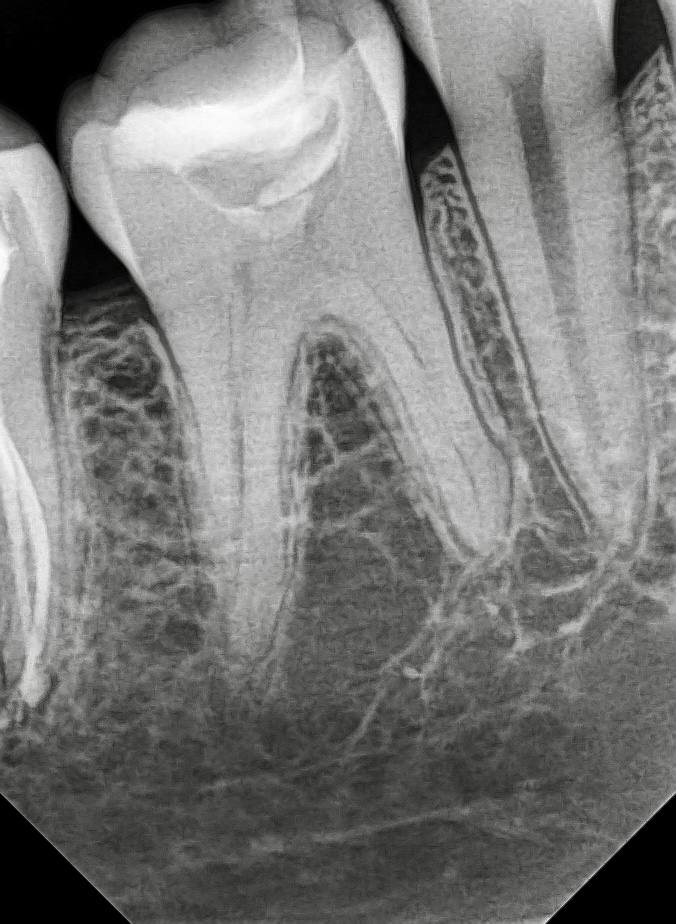

🦷 Облитерация корневых каналов после покрытия рога пульпы неизведанным веществом.

- Поиск корневых каналов твердосплавным бором